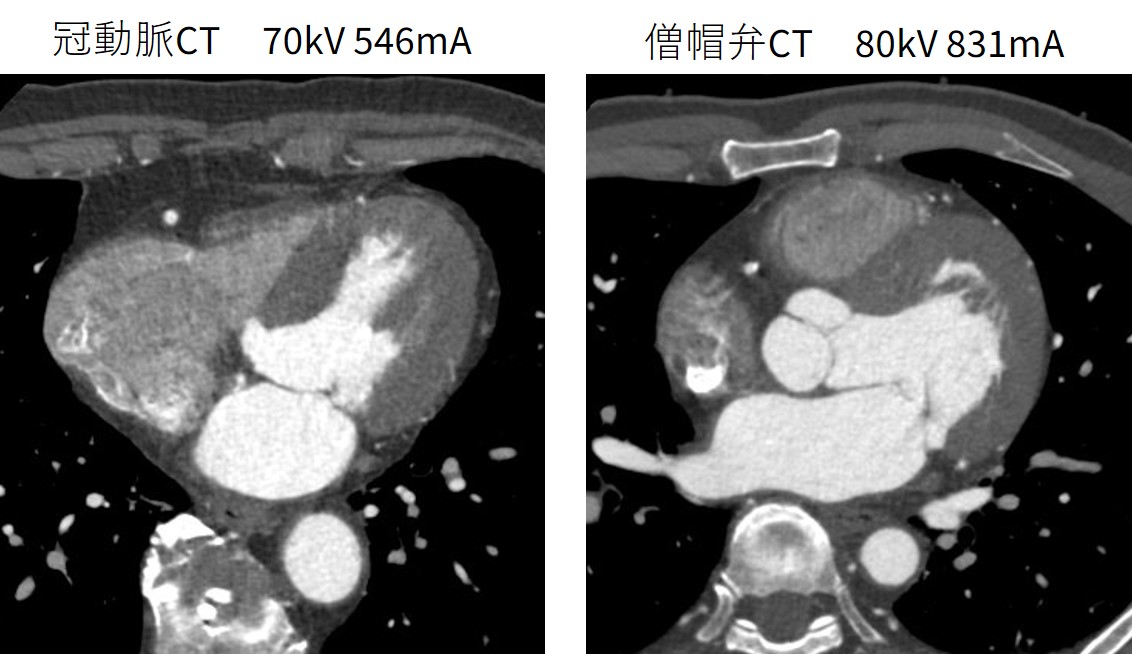

当院の冠動脈CTAにおけるSmart mA 設定は0.625mm Noise Index 28(Pre ASiR-V 70%)としている.一方,僧帽弁閉鎖不全症術前CTでは僧帽弁複合体も含めて評価を行うため,Noise Indexを24 (Pre ASiR-V 70%) としている.完全な1心周期の画像にて診断を行うためRetrospective gatingにてECG Dose Modulationを使用せず撮影を行う.そのため被ばく線量が多くなることからAuto Prescription(基準管電圧:80kV,Clinical Task:Soft Tissue + C High Contrast)を使用して体格に応じた最適な低管電圧での撮影を行っている.

Fig.4 冠動脈CT画像と僧帽弁閉鎖不全術前CT画像

当院の冠動脈CTにおけるCTDIvol の中央値は11.3 mGy(IQR:6.5 – 15.4 mGy),DLPの中央値は 174.8 mGy・cm (IQR:100.4 – 239.1 mGy・cm)であり,僧帽弁CTにおけるCTDIvol の中央値は21.7 mGy(IQR:15.7 – 32.1 mGy),DLPの中央値は 347.9 mGy・cm (IQR:250.4 – 513.1 mGy・cm)であり,僧帽弁CTは冠動脈CTと比較すると線量が多くなっている.しかし日本の診断参考レベル(DRLs2025)であるCTDIvol 57 mGy,DLP 940 mGy・cmを超過することなく撮影が可能である.